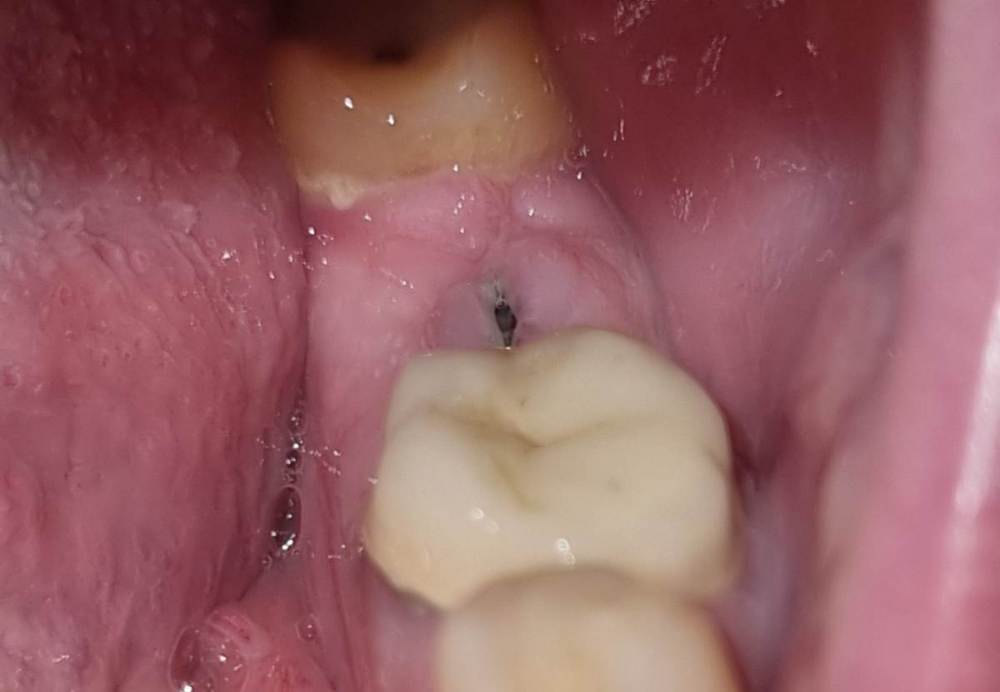

Chelovek2012 Опубликовано 10 февраля, 2024 Автор Поделиться Опубликовано 10 февраля, 2024 Прошло два месяца после имплантации. Сейчас выглядит так. По плану я должен через месяц пойти на следующую процедуру. Вопрос: можно ли отложить на месяц-два следующий этап? Ссылка на комментарий

Irouil Опубликовано 10 февраля, 2024 Поделиться Опубликовано 10 февраля, 2024 Можно, но на осмотр на плановый приём я бы все равно сходил 1 Ссылка на комментарий

Chelovek2012 Опубликовано 10 февраля, 2024 Автор Поделиться Опубликовано 10 февраля, 2024 (изменено) Думаете, слишком выступает визуально по фото, или есть другие подозрения? Изменено 10 февраля, 2024 пользователем Chelovek2012 Ссылка на комментарий